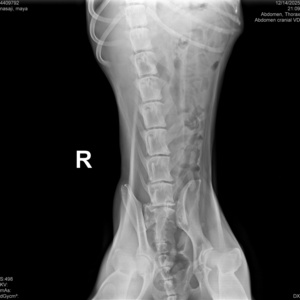

گالری تصاویر

رادیولوژی و سونوگرافی حیوانات در تهران